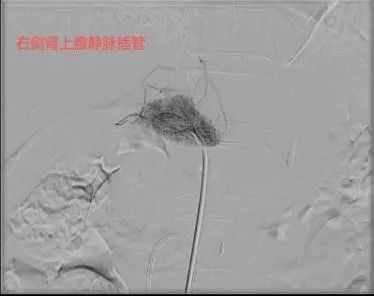

导管“寻路”:医生在X光引导下,通过血管造影精准导航,将导管送至肾上腺静脉,过程约30分钟。

58岁的杨先生患高血压多年,平日里血压控制不佳,近1年来出现血钾减低,间断进行补钾治疗后仍无法将血钾维持在正常范围。于是来到市四医院寻找原因,CT提示左侧肾上腺结节样增生,考虑杨先生存在原发性醛固酮增多症,为了明确双侧肾上腺的优势分泌侧来准确指导外科手术方案。医院介入室团队为患者进行了双侧肾上腺静脉采血术,血检结果提示左侧肾上腺为优势分泌侧。2周后,杨先生在泌尿外科接受了腹腔镜下左侧肾上腺切除术,术后血压恢复正常,无需药物辅助控制。